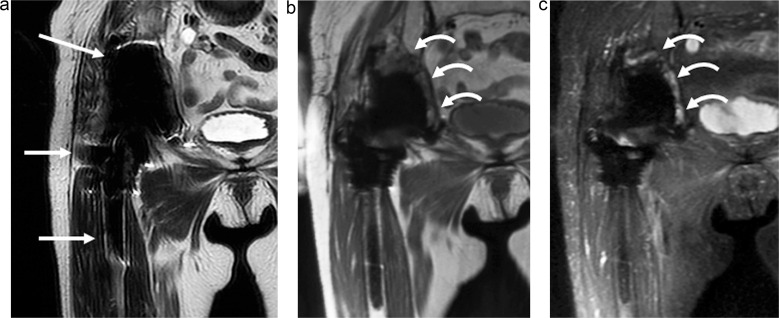

Results: Thirty-seven hip joints in 24 Asian patients (age = 73.9 ± 10.8 years; 18 females) were included. Twelve hip joints (32%) had PJI; seven underwent a surgical intervention. The significant findings for hip PJI included periosteal edema of the acetabulum, intermuscular edema, intramuscular fluid collection, and lymphadenopathy (P < 0.05). In the cases with surgical intervention, the significant findings included capsular distension, capsular thickening, an osteolysis-like pattern of the femur, subcutaneous fluid collection, and lymphadenopathy (P < 0.05). The MRI impressions had high diagnostic significance for both hip PJI cases and those with surgical intervention (P < 0.001). The MRI impression was more significant for hip PJI than the other clinical markers (P < 0.05), while the other clinical markers were more significant in the cases with surgical intervention (P < 0.05).

Conclusion: The significant findings in the hip PJI cases included acetabular periosteal edema, intermuscular edema, intramuscular fluid collection, and lymphadenopathy. The significant findings in the cases with surgical intervention included capsular distention, capsular thickening, a femoral osteolysis-like pattern, subcutaneous fluid collection, and lymphadenopathy. The utilization of MAR MRI demonstrated great diagnostic significance for hip PJI.